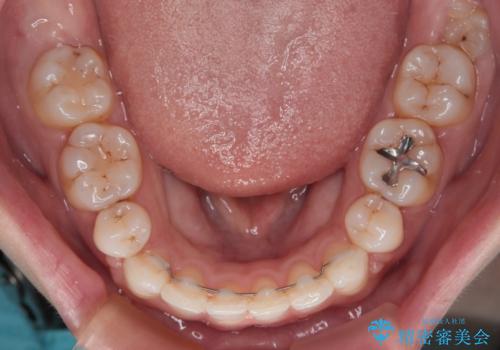

唇が閉じにくい ワイヤー装置での抜歯矯正

上下ともに前歯が少し舌側に傾斜したような仕上がりとなりましたが、口が閉じやすくなったとのことで、患者様には大変満足していただけました。